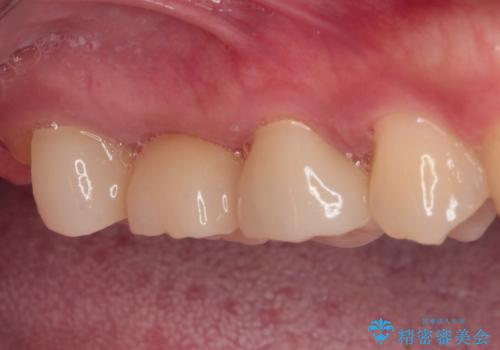

壊れやすいブリッジ インプラント治療で安定した咬み合わせに

- 頻繁に脱離を繰り返す奥歯のブリッジが欠けてしまったとのことで来院された患者様です。

外科処置を回避するためにブリッジ治療を選択されたそうですが、頻繁に脱離するので、欠けた部分のクラウンの作り替えと、欠損部のインプラント治療を行うこととしました。

最後方歯は、クラウンを維持するための高さが不足していたため、インプラント処置の際に歯冠長を延長する手術を併用し、維持力を増すこととしました。

上顎洞までの骨高さが低いケースでしたが、ショートインプラントと骨圧縮機能を持つドリルの使用により、上顎洞底挙上を行うことなく、インプラント治療を行うことができました。